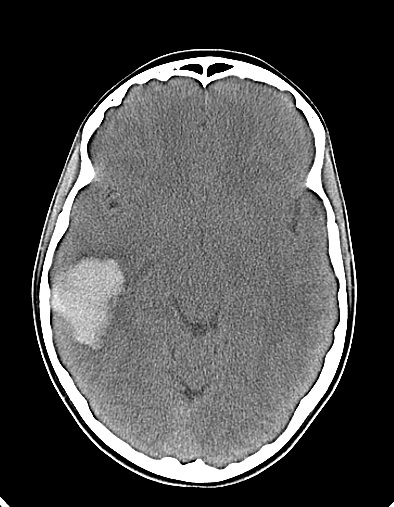

Diagnóstico de Malformação Arteriovenosa Cerebral após Traumatismo Craniano

Images in Pediatrics